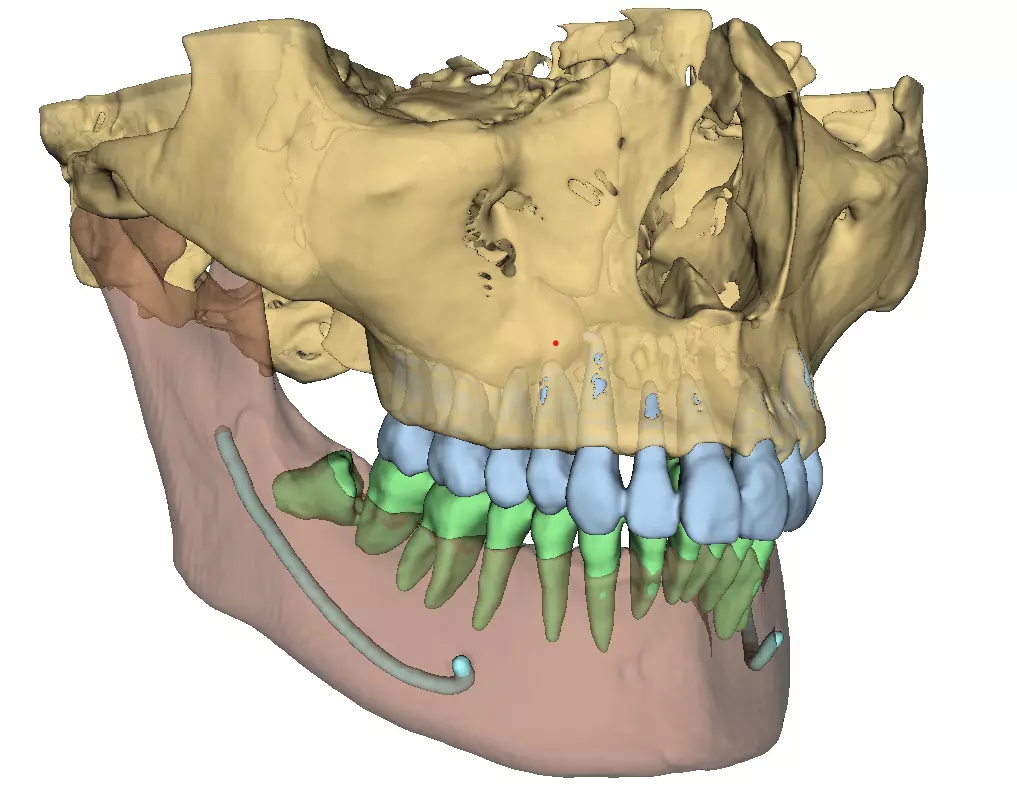

Split into parts

13